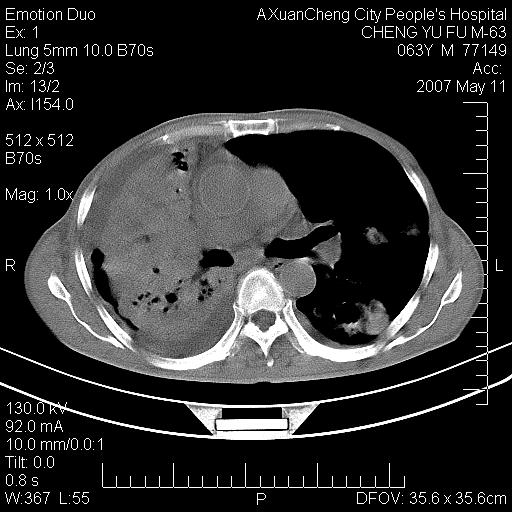

以下是引用小初学者在2007-5-11 19:32:00的发言:[br]1、首先考虑干酪性肺炎支气管播散[br]2、支气管肺泡癌待排

以下是引用zhangzhongshou在2007-5-11 19:30:00的发言:[br]细支气管肺泡癌可能性大。